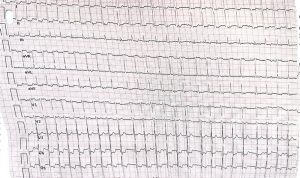

A 28 year old nurse with a long history of paroxysmal palpitations has the following 12-lead ECG and 2-channel telemetry trace recorded during an episode.

Read more and find your answer

Haris M. Haqqani August 2022